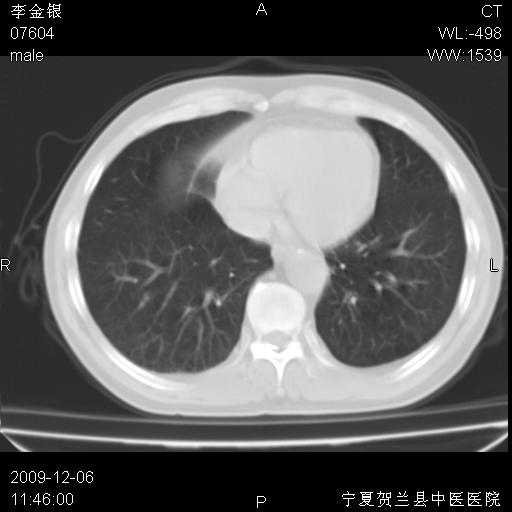

该病人 ,男,62岁,主因咳痰带血两天

考虑右肺中央型占位性病变并阻塞性肺炎.(右肺上叶支气管变窄),建议支纤镜检查.

考虑右肺中心型肺癌伴阻塞性肺炎及右肺门淋巴结转移,建议纤维支气管镜进一步检查。

支气管壁明显增厚 管腔狭窄,腔静脉后多个淋巴肿大,结合年龄病史考虑右肺上叶中央型肺癌并阻塞性肺炎

右肺上叶后段支气管阻塞,右上肺门占位,相应肺段阻塞性肺炎,右肺门有淋巴结肿大。诊断右肺上叶中心型肺癌,阻塞性肺肺炎、右肺门淋巴结转移。

右上叶支气管狭窄,管壁增厚,远端斑片状软组织影,病灶邻近叶间裂,叶间裂无移位。

诊断右肺中央型肺癌。

那个片影应该大部分都是病灶,病灶沿肺段支气管分支生长,后段完全显示不清、闭塞。若为不张应该伴有叶裂的移位,若为炎症应有空气支气管征。

考虑右侧中央型肺癌伴右肺上叶后段阻塞性炎症、肺不张、右肺门和纵隔淋巴结肿大。

右肺上叶中心型肺癌,阻塞性肺炎、右肺门和纵隔淋巴结转移。